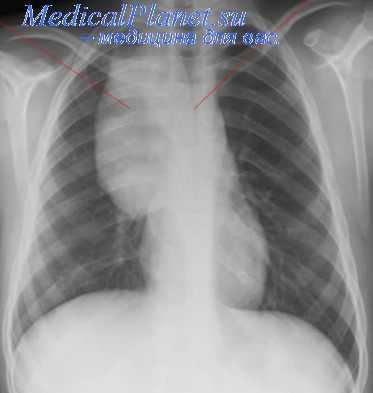

Всем больным необходимо производить прямую и боковую рентгенографию органов груди. У ряда больных очень показательные данные удается получить путем томографии. Для более рельефного выявления различных новообразований средостения большую ценность имеет так называемая пневмомедиастинография, т.е, рентгенография после введения в клетчатку средостения воздуха или кислорода, который вводят под местной анестезией за рукоятку грудины, под мечевидным отростком или около края грудины в одном из межреберных промежутков в количестве от 500 до 1000 см 3 . При анализе пневмомедиастинограмм – или пневмомедиастинотомо-грамм, который должен быть произведен квалифицированным рентгенологом, в большинстве случаев удается достаточно точно определить локализацию, размеры и другие особенности имеющегося новообразования.

При рентгенологическом исследовании больных с неврогенными опухолями обнаруживают округлую гомогенную тень, которая имеет ровные контуры и располагается в задних отделах средостения, примыкая к позвоночнику или к задним отрезкам ребер. Она особенно хорошо контурируется после наложения пневмомедиастинума или пневмоторакса.